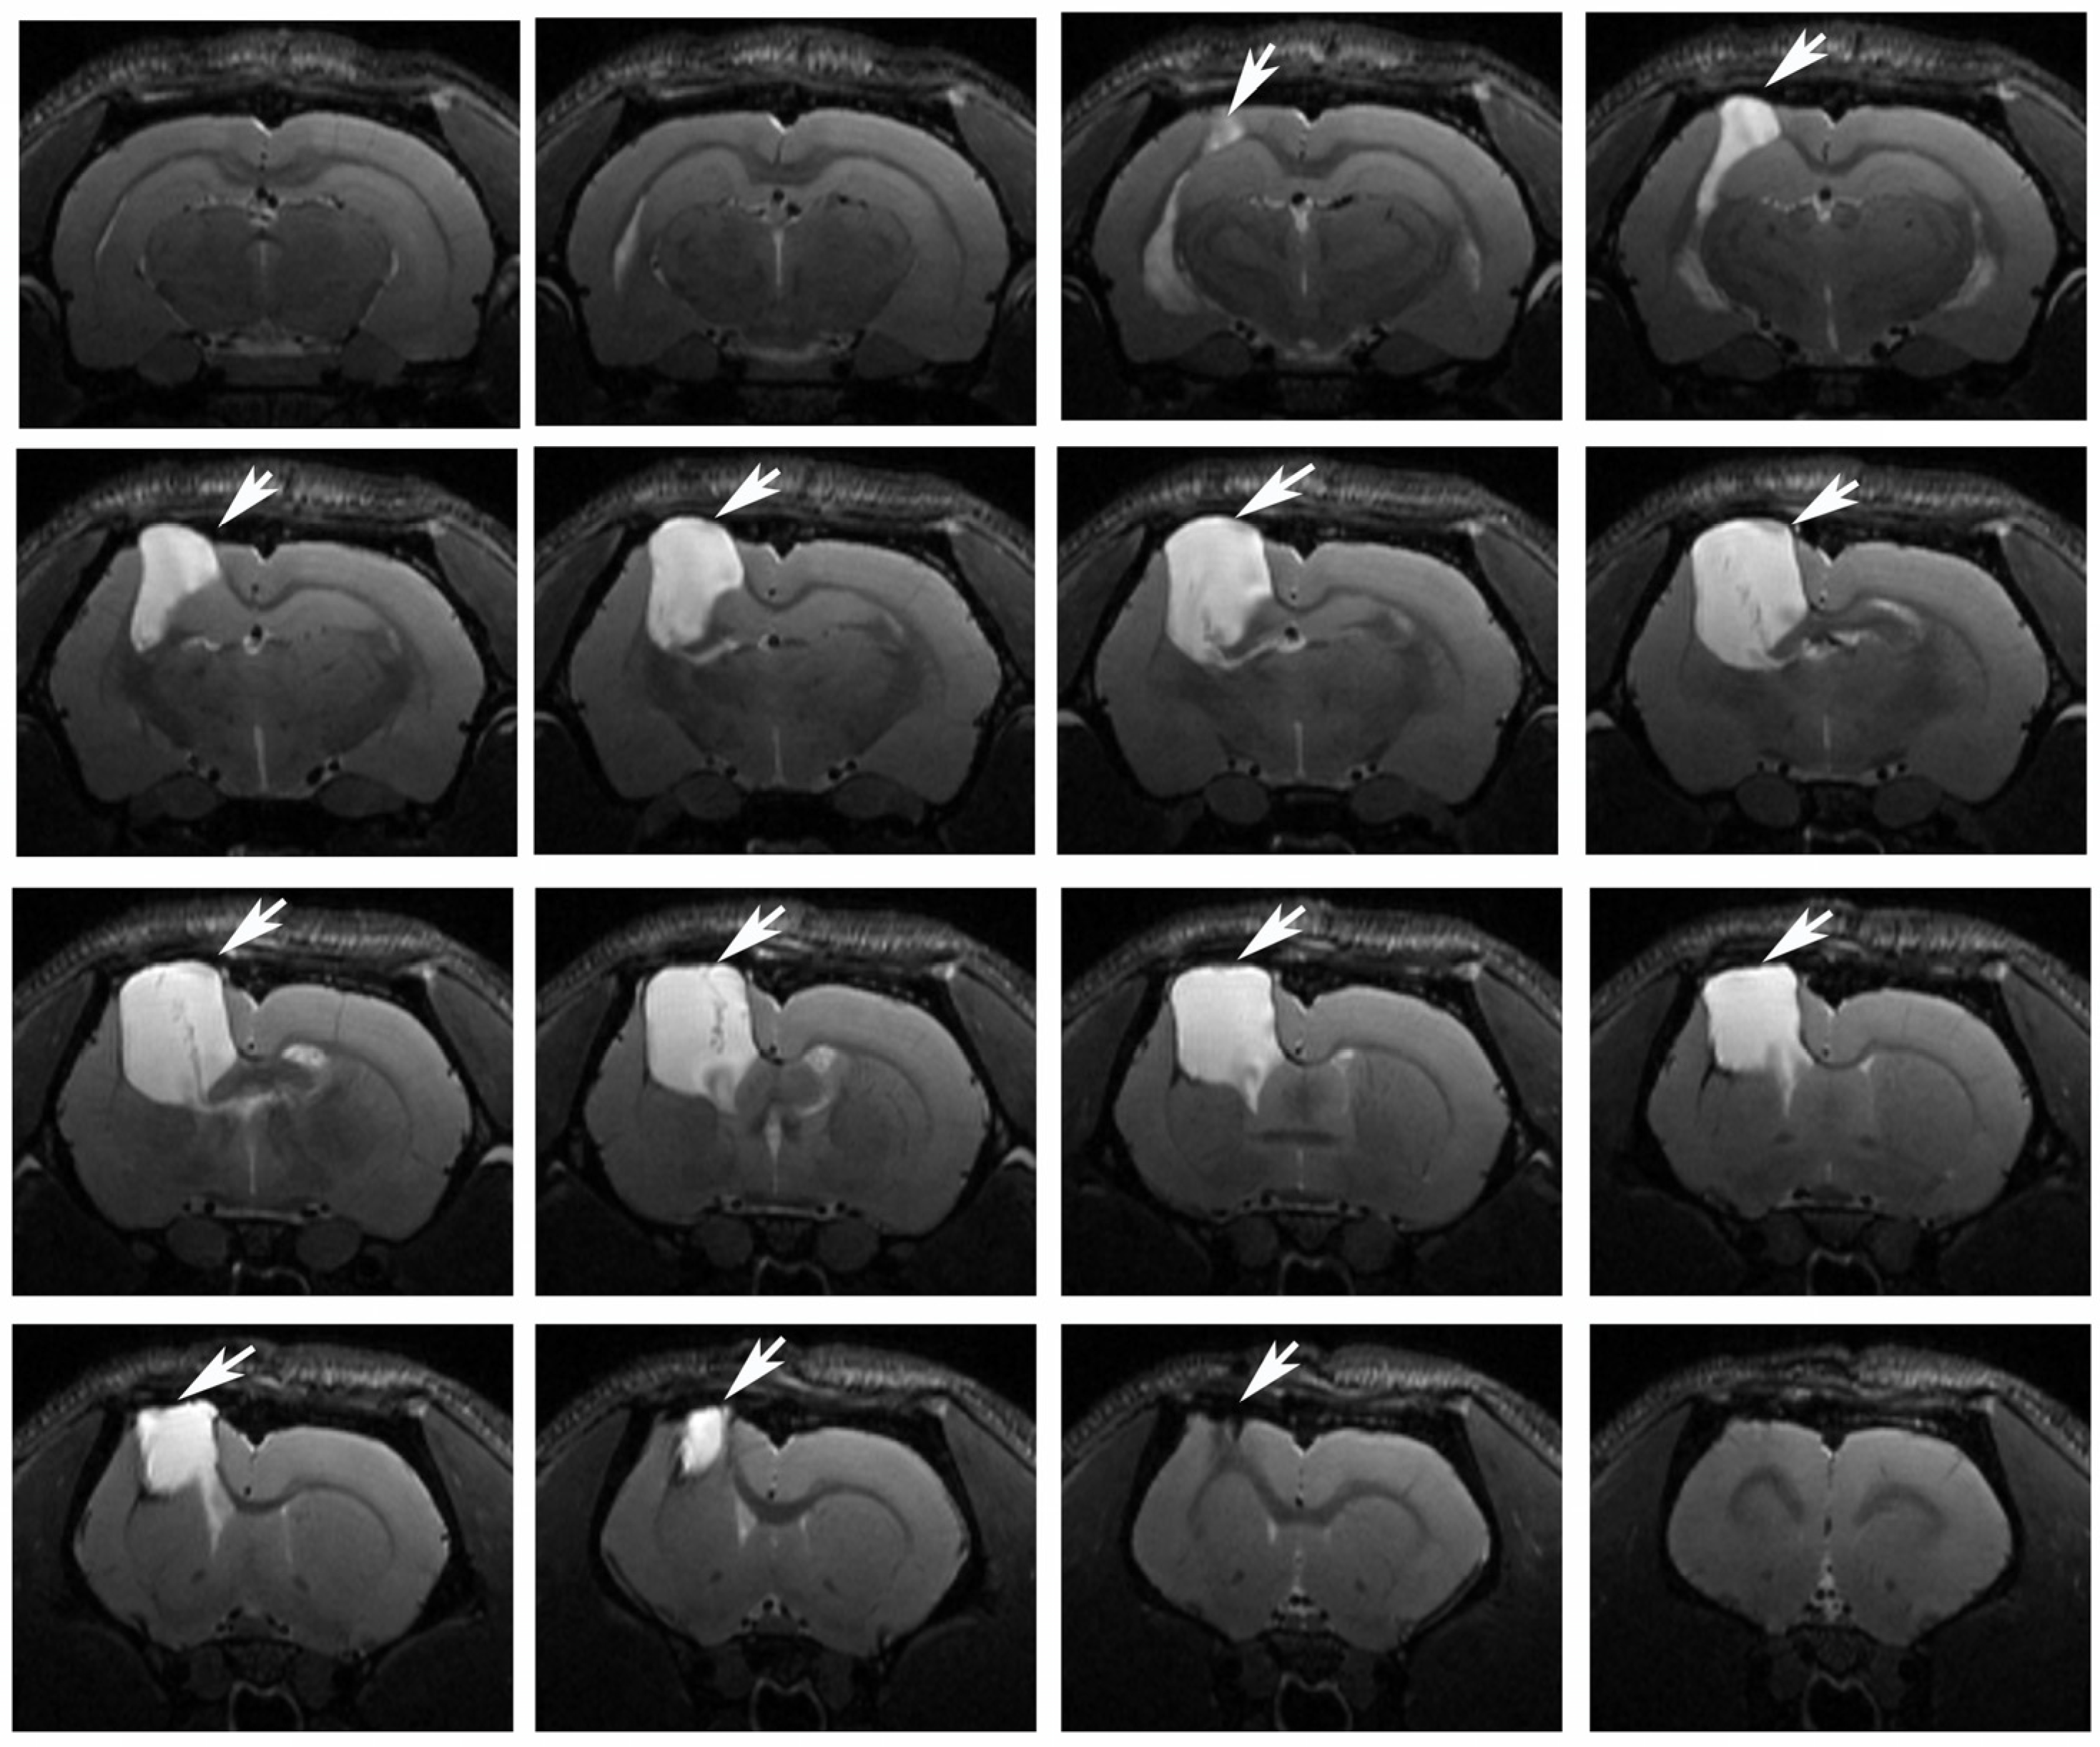

The long-term effects of traumatic brain injury on the size of the lesion resulting from unilateral focal TBI in rats were investigated using the MRI method. On the 180th day after surgery, T2-weighted MR images detected a clear focus of injury in the sensorimotor cortex, in a large part of the corpus callosum, a damage to the striatum and a dilatation of the lateral ventricle in the left (injured) hemisphere of the brain (Figure 6). Based on MR images of the brain, when the rats were injected monthly, the morphometry of the damaged area did not show a significant difference in the volume of the focus in groups of animals that were injected with MB or only saline. The average size of the focus in untreated animals was 41 ± 3 mm3, in treated ones—44 ± 3 mm3.

Figure 6.

Magnetic resonance images of one experimental rat brain on the 180th day after traumatic brain injury. The left hemisphere, corpus callosum, cortex, and striatum are damaged (the damaged zone is indicated by an arrow).

The brains of the animals were examined in the long-term period after the injury (six months later). According to the obtained MRI data, by that time a distinct lesion was formed in the left (damaged) hemisphere of the brain, in which the sensorimotor cortex and most of the corpus callosum were destroyed; the striatum was also damaged. It should be noted that an increase in microglial density was observed in the marginal zone of the destruction focus compared to the control animals, indicating the presence of a long-term inflammatory process in the damaged hemisphere in animals with TBI, since the activation of these cells mediates the release of pro-inflammatory mediators (cytokines, chemokines, interleukins, tissue necrosis factor, etc.) [28].

The study of rat brains using MRI did not find a significant difference in the volumes of foci in MB-treated and untreated animals. However, earlier in the study of the neuroprotective action of MB 7–14 days after TBI, MB was shown to reduce the volume of the focus [11,41]. At the same time, a previously conducted study of delayed (one to six months) TBI-caused damage of brain structures did not find a correlation with neurological deficits [42]. The development of the focus in TBI is known to take a very long time [43], whereas inflammatory and degenerative processes are inextricably associated with oxidative damage [44,45]. Thus, apparently, the neuroprotective effect of MB during prolonged development of the secondary damage is primarily aimed at rehabilitation of diffuse damage as well as reduction in inflammation and therefore in oxidative damage to tissue.